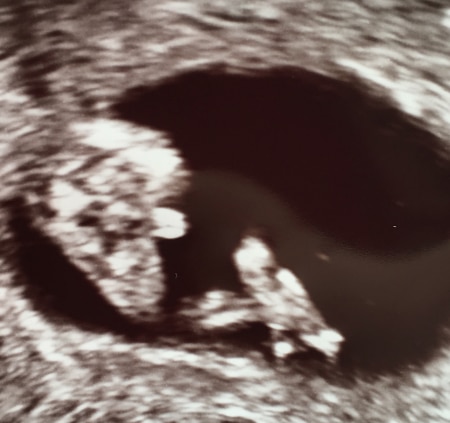

Hallo ihr Lieben! Würde einfach mal gerne wissen, was ihr sagt

Ich erkenne zwar nicht viel Aber ich würde auf junge tippen

Ich glaub ich sehe Hoden und Penis

hab ich auch gedacht. also ich sehe hoden und penis.

3 Striche kann ich beim besten Willen nicht erkennen aber deutlich Hodensack und Penis. Hätte ich so ein Bild dann würde ich mich schon sehr drauf verlassen glaube ich.

Eher junge. Mein Mädchen hat damals weniger äußerlich gehabt

Muss wohl dazu sagen, dass ich da 11+2 war

Mädchen.